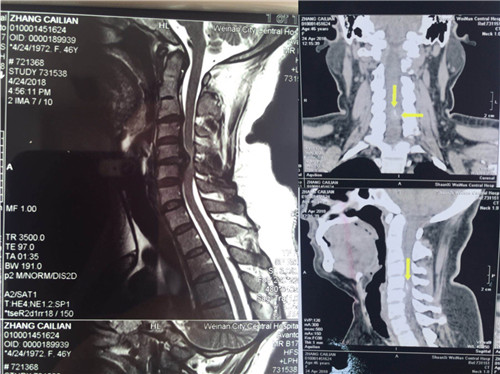

入院后,骨一科医师对患者做进一步检查。颈椎CT显示,颈5/6椎间盘突出,颈3/4、4/5、6/7椎间盘突出;颈椎MR显示,颈4/5、6/7椎间盘突出,颈5/6椎间盘突出并椎管狭窄。

术前